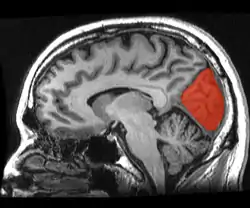

Cuneus

The cuneus (from Latin 'wedge'; plural cunei) is a smaller lobe in the occipital lobe of the brain. The cuneus is bounded anteriorly by the parieto-occipital sulcus and inferiorly by the calcarine sulcus.

![]() Sagittal MRI slice with the cuneus and lingual gyrus shown in red. | |